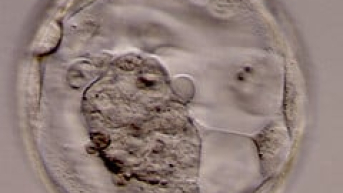

Já nos primeiros três dias da 3º semana, este zigoto se desloca até o útero. Ao mesmo tempo, começa a se dividir formando o blastocisto2, uma bola maciça de células dentro de uma camada cheio de líquido. Todo este processo é gerenciado pelas liberação de hormônios. Assim que chega ao útero, começa a implantação ou nidação no endométrio.

Com o término da 4ª e última semana do primeiro mês, a implantação é concluída. O blastocisto se divide em trofoblasto, que formará a placenta, e embrioblasto, que já representa o minúsculo embrião. Teoricamente, a gestação pode ser descoberta nesta fase. Mas recomenda-se esperar a quinta semana e alguns dias de atraso para comprovação da gravidez com um ginecologista, já que o feto com 1 mês não pode nem ser visto pelo exame de ultrassom3.

Ao completar o 1° mês de gestação, o embrião é tão minúsculo que pode ser comparado a um grão de arroz, medindo em torno de 5 mm. Ainda não tem formas e somente nas próximas semanas que se iniciará o desenvolvimento do tubo neural, de onde surgirá o cérebro e a medula.